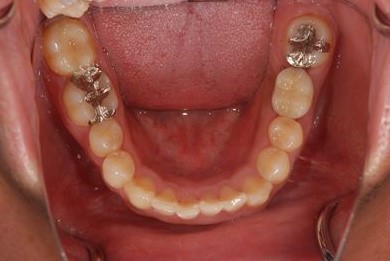

インプラントの症例写真 IMPLANT

抜歯即日スピードインプラント治療

| 性別/年齢 | 男性 / 38歳 | ||||||||||||||||||||||||||||||||

| 主訴 | 10年位前に虫歯治療をした右下奥歯のつめ物が取れ、再治療を受けた際にインプラントをすすめられたため、治療相談で来院。 | ||||||||||||||||||||||||||||||||

| 治療方針 | 抜歯と同時にインプラントを埋入し、治療期間を短縮する。 | ||||||||||||||||||||||||||||||||

| 治療内容 | インプラント1本(抜歯即日スピードインプラント)、ハイブリッドセラミッククラウン1本 | ||||||||||||||||||||||||||||||||